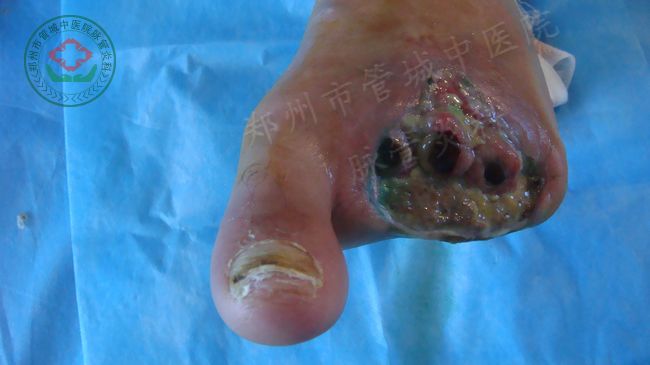

一位贵州的脉管炎患者

入院诊断:

中医诊断:脱疽

湿热毒盛型

西医诊断: 血栓闭塞性脉管炎

第三期二级(坏死期)